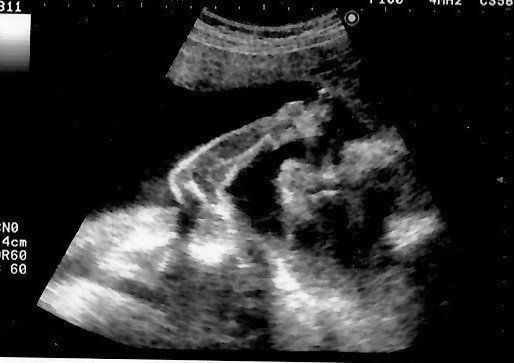

妊娠29週目のエコー写真 3Dのエコー画像撮影にチャレンジ

わざわざ別の産院に出向き、高い料金を払って3D画像撮影に挑んだものの、なんと、撮影した時間帯の赤ちゃんはおなかに向かって後ろ向きにおねんね中。残念ながら期待していたような顔がわかる3D画像は撮影できませんでした。それでも、2D画像ではわからなかった腕や後ろ姿が鮮明に写っており、とても興奮しました。